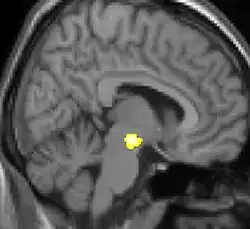

| La morphométrie voxel par voxel (VBM) montre les différences structurelles des zones du cerveau | ||

Les images par tomographie à émission de positron indiquent les régions du cerveau qui sont activées lors de la douleur, par rapport aux périodes sans douleur. Elles montrent les régions du cerveau qui sont toujours actives durant la douleur en jaune/orange (appelé "matrice-douleur"). La zone au centre (dans les trois vues) est spécifiquement activée uniquement pendant la crise. Les photos sur la ligne du bas (effectuées par VBM) montrent les différences structurelles entre les patients souffrant d'AVF et des personnes saines : seulement une partie de l'hypothalamus est différente[50],[51].

Il semble exister des anomalies microstructurales hypothalamiques bilatérales (en l'occurrence l'existence d'une hypertrophie)[52] sans que l'on sache si ces anomalies sont la cause ou la conséquence de la répétition des crises.